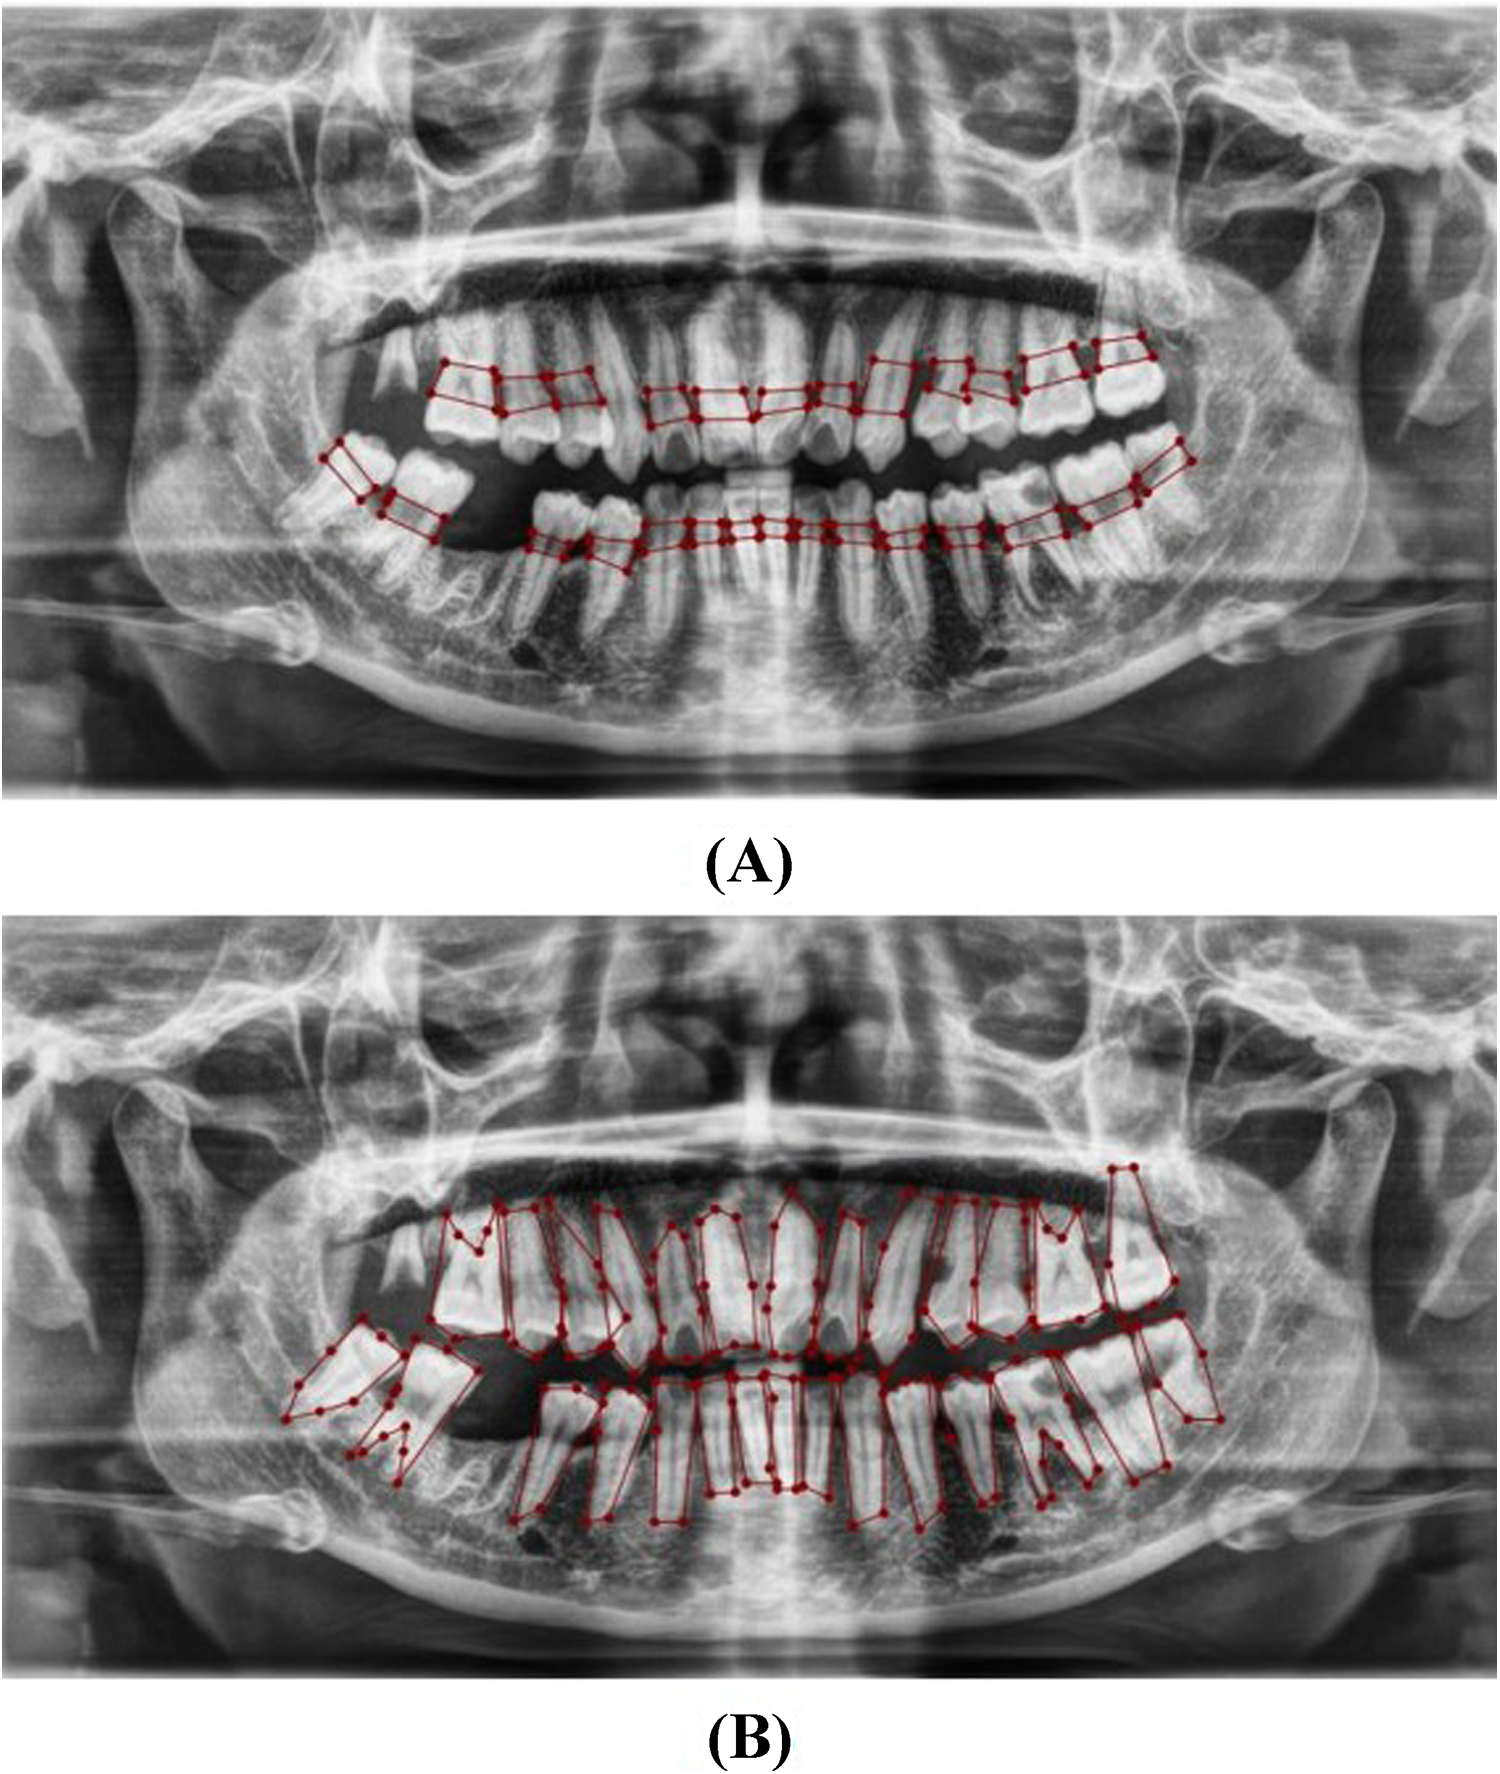

Localization and Classification: The model was trained to identify and localize the region between the cemento-enamel junction (CEJ) and the alveolar bone crest, producing bounding boxes or heat maps for further analysis (Figure 5).

Figure 5

Image showing the predicted area between the CEJ and the alveolar bone crest (A), and teeth segmentation (B).